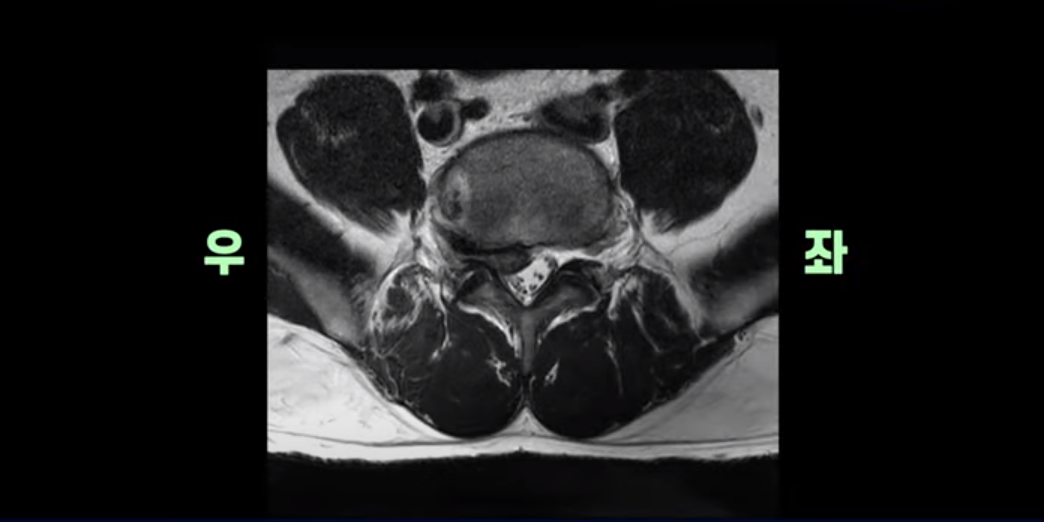

MRI를 보면 이분 5번 1번 디스크가 심하게 터져서 밀려 올라가 있습니다.

횡단면을 보면 우리 병원 치료 후기에 있는 다른 디스크 파열 환자분들에 비해서는 파열이 덜 심해 보일 수도 있지만,

이분은 파열이 오른쪽으로 치우쳐 신경이 빠져나가는 추간공을 완전히 막고 있습니다.

다른 신경 구멍들은 열려있는데 비해 5번 1번 구멍은 까맣게 막혀있습니다.